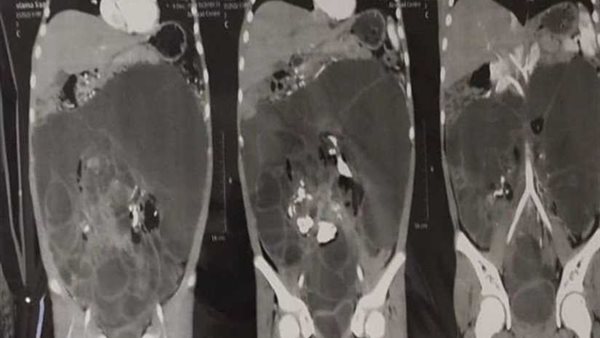

ومن جانبه أوضح الدكتور ماهر مختار مدير مستشفى الأطفال الجامعي بأسيوط أن أهل الطفلة لاحظوا وجود انتفاخ بشكل غير طبيعي في البطن، ما استدعى توجههم لمحافظة أسيوط لفحص الحالة بمعرفة أحد الأساتذة المتخصصين، وهو ما قام به الدكتور محمد مدحت نصر مدرس الجهاز الهضمي الذي أجرى عددًا من الفحوصات التي أثبتت وجود ورم ضخم في بطن الطفلة يستدعي استئصاله.

وأضاف الدكتور طارق صبرة مدرس واستشاري الجراحة العامة وجراحة الأطفال أن حالة الطفلة كانت تستدعي جراحة دقيقة لاستئصال الورم بشكل كامل والذي كان يشمل معظم محيط البطن وناشئ من المبيض الأيسر وهو ما تم شرحه لأسرة الطفلة للموافقة على إجراء العملية حيث تم تشكيل فريق طبي تحت رعاية الدكتور إبراهيم علي رئيس وحدة جراحة الأطفال بالمستشفى وبرئاسة الدكتور طارق صبرة، ويضم الدكتور حسين إبراهيم فرح المدرس المساعد بقسم جراحة الأطفال والطبيب أحمد كامل الطبيب المقيم بالقسم إلى جانب فريق التخدير والذي يضم الدكتورة سهام معين الأستاذة المساعدة بقسم التخدير والدكتور أيمن عبد الخالق المدرس بالقسم والطبيب محمد سالم حيث نجح الفريق الطبي في استئصال الورم بالكامل في جراحة استغرقت ثلاث ساعات مع المحافظة على المبيض والأنبوبة الرحمية وتعافي الطفلة بشكل كامل.